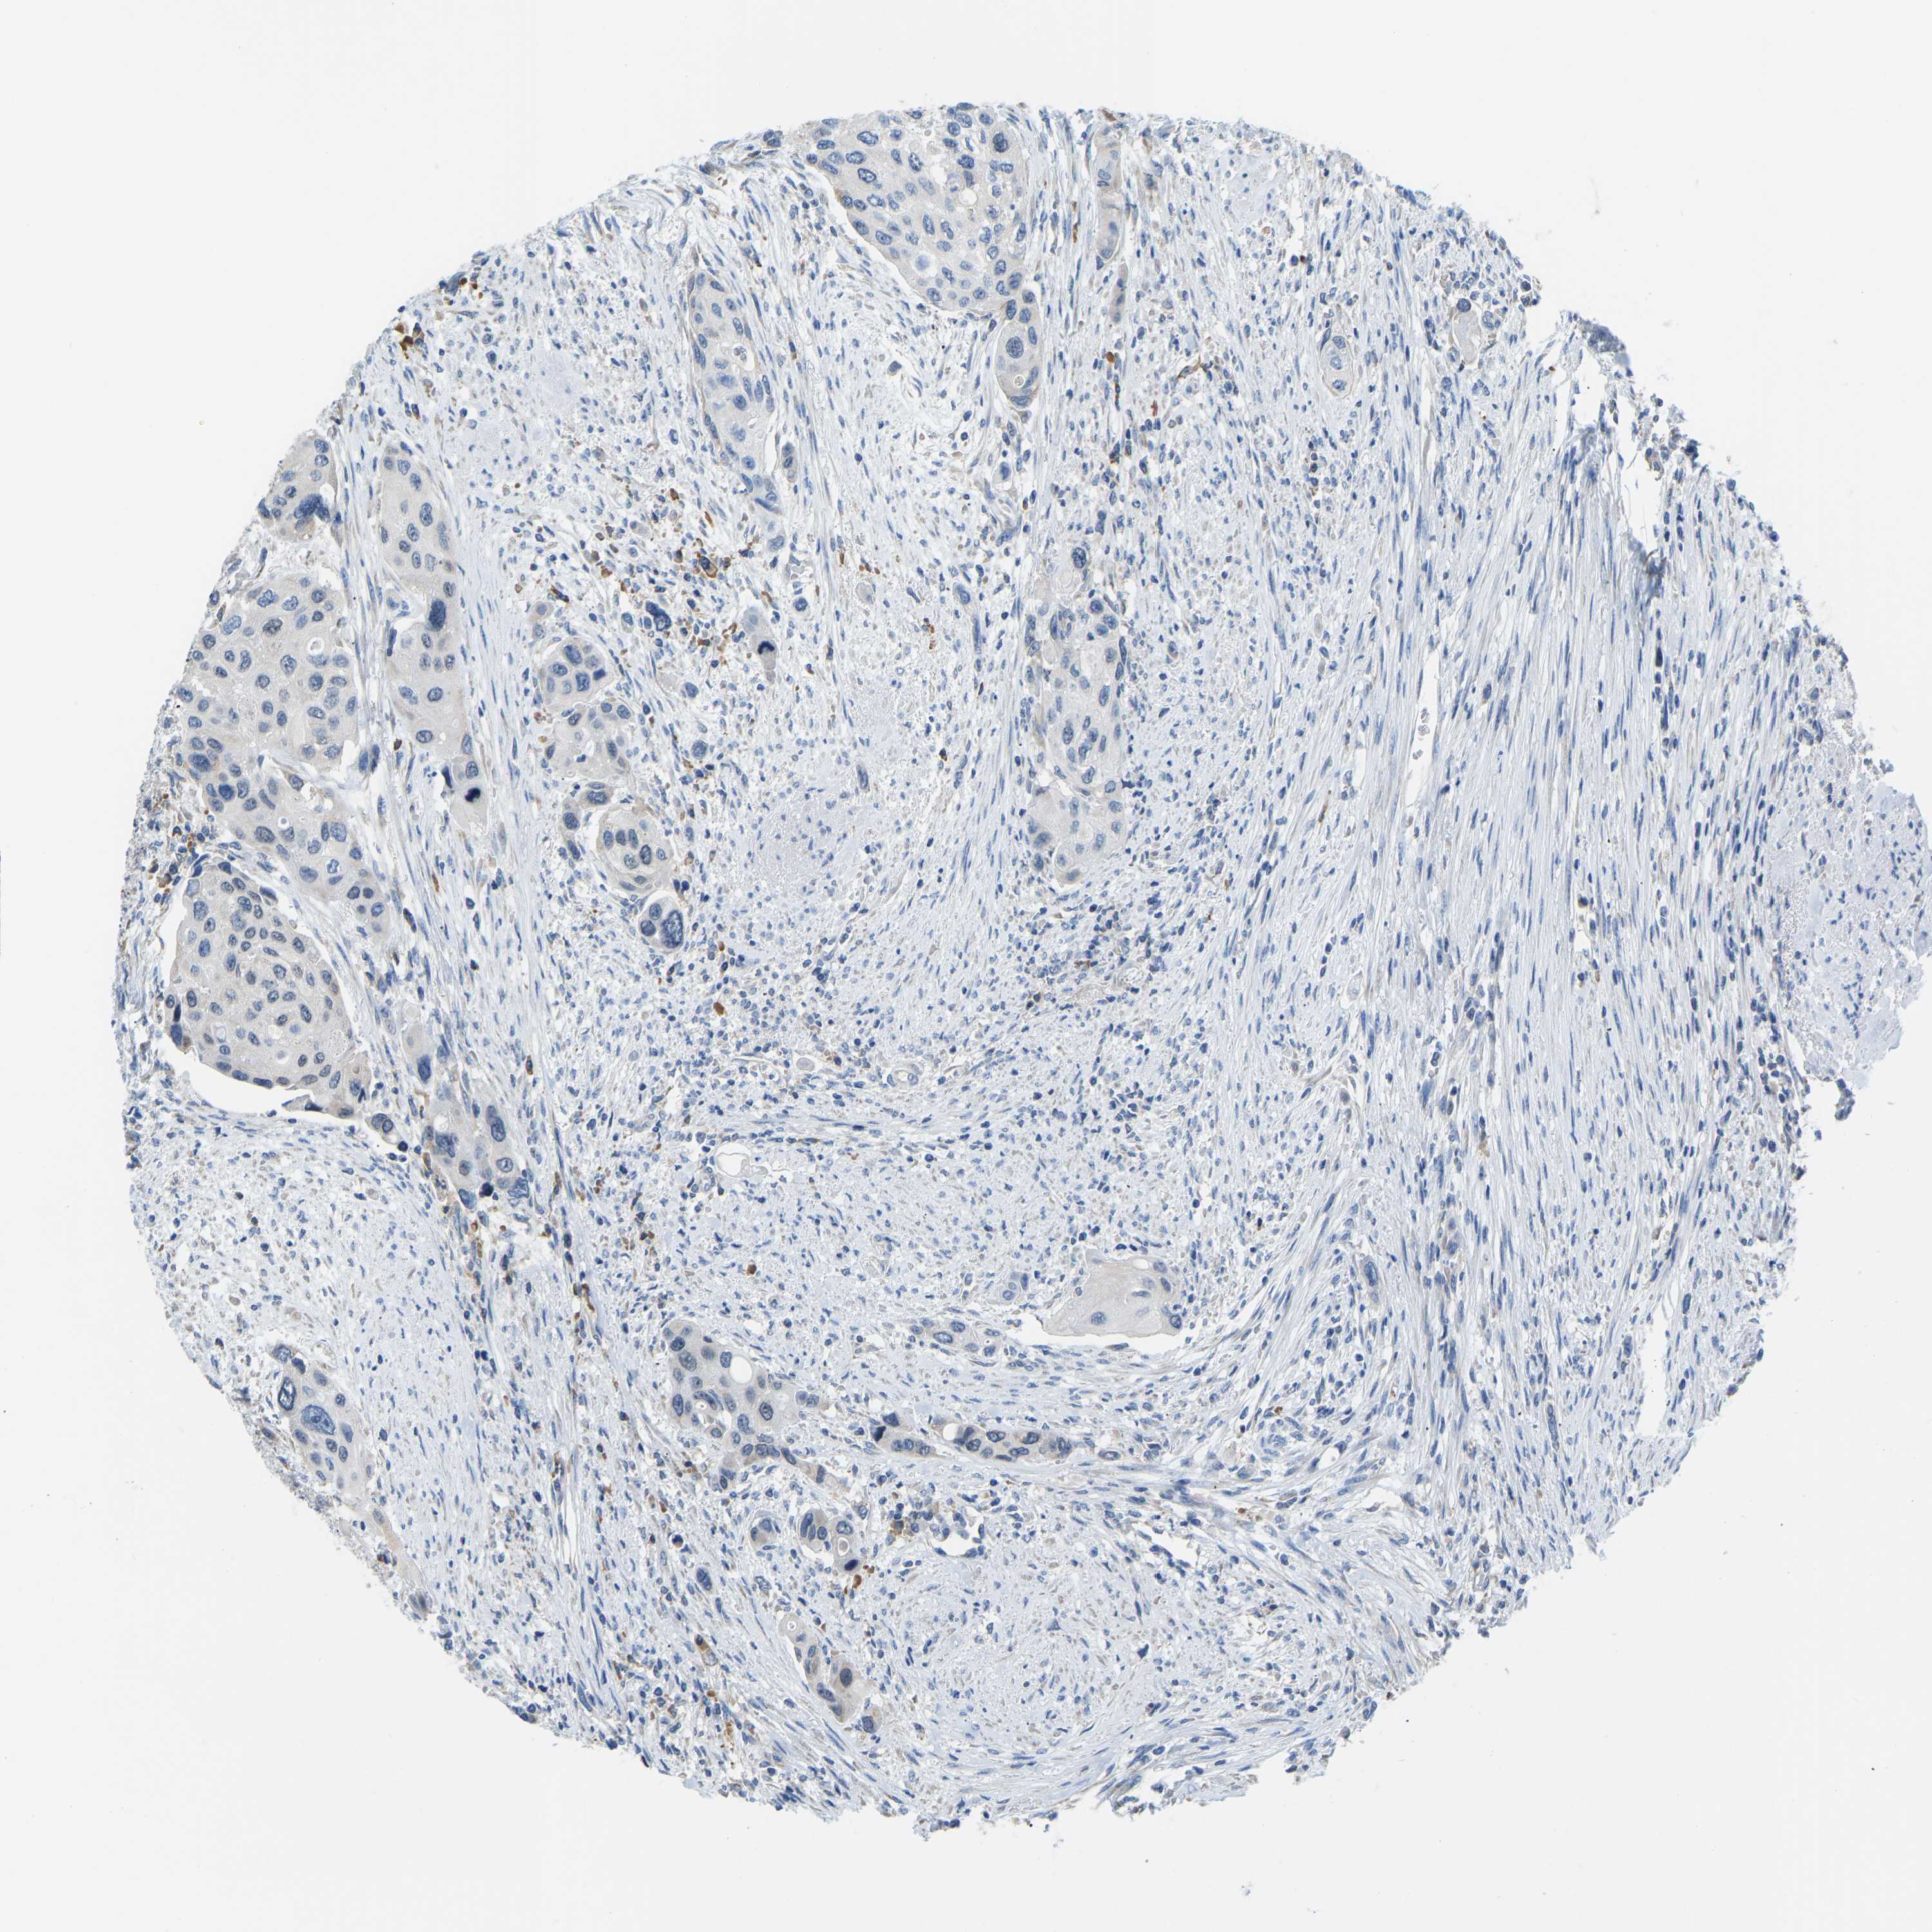

UROTHELIAL CANCER - Protein expressioni

A mouse-over function shows sample information and annotation data. Click on an image to view it in a full screen mode. Samples can be filtered based on level of antibody staining by selecting one or several of the following categories: high, medium, low and not detected. The assay and annotation is described here.

Antibody stainingi

Antibody staining in the annotated cell types in the current human tissue is reported as not detected, low, medium, or high, based on conventional immunohistochemistry profiling in selected tissues. This score is based on the combination of the staining intensity and fraction of stained cells.

Each image is clickable and will lead to virtual microscopy that enables deeper exploration of all samples and also displays staining intensity scores, fraction scores and subcellular localization as well as patient and tissue information for each sample.

Antibody HPA000660

Urothelial carcinoma, High grade